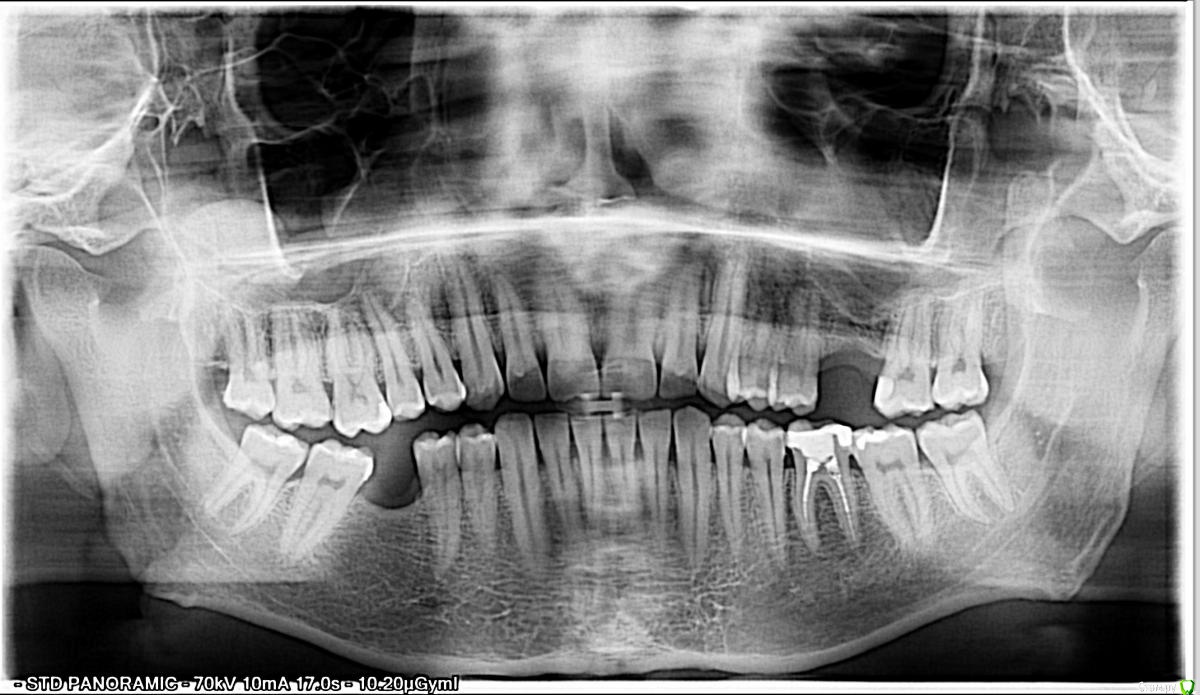

Valery17 Опубликовано 19 октября, 2015 Поделиться Опубликовано 19 октября, 2015 (изменено) Снимок до того как полечили кариес снизу слева между 5 и 6 зубами. Говорят если я правильно понял что слева сверху, на 5ке вроде кариес на контакте и что там очень близко к нерву, типа нужно лечить пульпит. Никаких болей нету, ничего не болит. Так ли это? И ещё где-то нужно поменять пломбу не запомнил в каком правда месте, потому что канал не до конца запломбирован и можно будет потерять зуб. Объясните что видите вы, потому что в одной поликлинике у меня проблемных мест не нашли, а в этой сразу 3 нашли. Спасибо. Изменено 19 октября, 2015 пользователем Valery17 Ссылка на комментарий

pils Опубликовано 19 октября, 2015 Поделиться Опубликовано 19 октября, 2015 И кариес, и не до конца запломбированные каналы есть.А по поводу боли, так это лишь один из многих клинических симптомов.Информация к размышлению1. Девушку со студенческих лет помню - рак околоушной слюнной железы, четвертая стадия. Боли? Какие боли? Полностью асимптоматичен...Есть ли суслик в этом случае? Так не болит же!2. С асимптоматичной проблемой Вы пришли, Вам улыбнулись, все вылечили, Вы заплатили сравнительно немного и ушли.3. С болями Вы попадаете на пару неприятных долгих визитов.4. Мой личный прайс кариеса и пульпита в сумме дает различие два-три раза. А так как экономика должна быть экономной, разумнее решать проблему до появления осложнений. Машину-то я на сервисное обслуживание отдаю до того, как она умрет по дороге в любимую Ригу. Но это железяка, а тут речь о собственном здоровье. Риторический вопрос, который часто хочу задать многим пациентам - зачем Вы идете к врачам, которым не доверяете? 1 1 Ссылка на комментарий